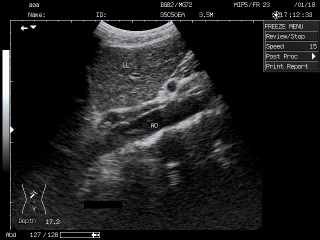

Die Ultraschalluntersuchung ist eine bildliche Darstellung der Strukturen und Organe des Körpers mittels Ultraschallwellen.

Organe und benachbartes Gewebe reflektieren den Ultraschall unterschiedlich. Diese Reflektionen werden über einen Verstärker am Bildschirm sichtbar gemacht. Mit Hilfe der Ultraschallwellen kann man eine räumliche Vorstellung von Größe, Form und Struktur der untersuchten Organe verschaffen.

Während der Sonografie liegt der Patient auf einer Untersuchungsliege. Für ein gelungenes Ultraschallbild ist ein unmittelbarer und luftfreier Kontakt zwischen Haut und Schallkopf notwendig. Deswegen wird auf den Schallkopf ein Gel aufgetragen und über den zu untersuchenden Körperteil bewegt. Daruch kann man die Organe und Gewebe aus verschiedene Richtungen am Bildschirm ansehen.